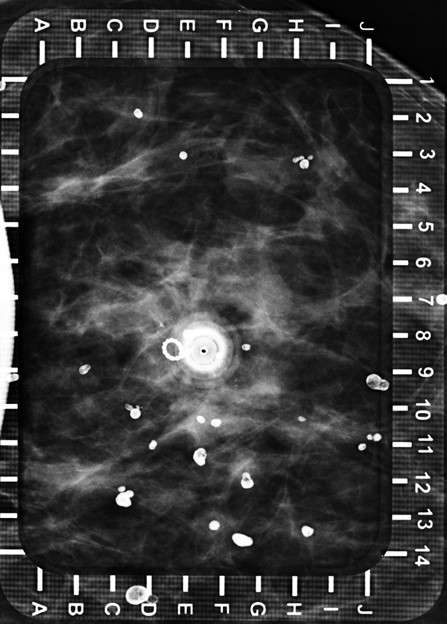

Technologist takes 2D or 3D mammogram with wire(s) in place (Figure 4).

Radiologist evaluates for adequate placement.

Procedure Mammographically Guided Wire Localizations Figure 4

Figure 4: Left: Final image with wire in place (inside the hollow needle). The end of the wire hook is appropriately located just beyond the residual microcalcifications. Right: Surgical specimen radiograph confirms removal of microclip and microcalcifications along with the wire.